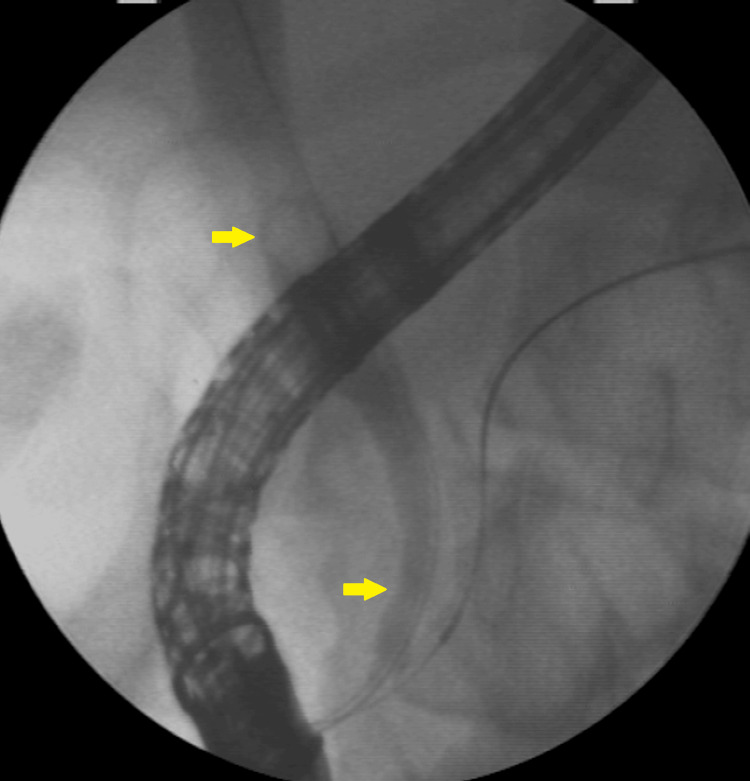

Mechanical lithotripsy was unsuccessful in fragmenting the stone, and a complication arose when the proximal rod of the basket broke, making it challenging to remove the basket along with the trapped stone (Figure 8).

A second 15-mm dilation was performed to remove the imprisoned basket along with the calculi (Figure 9).